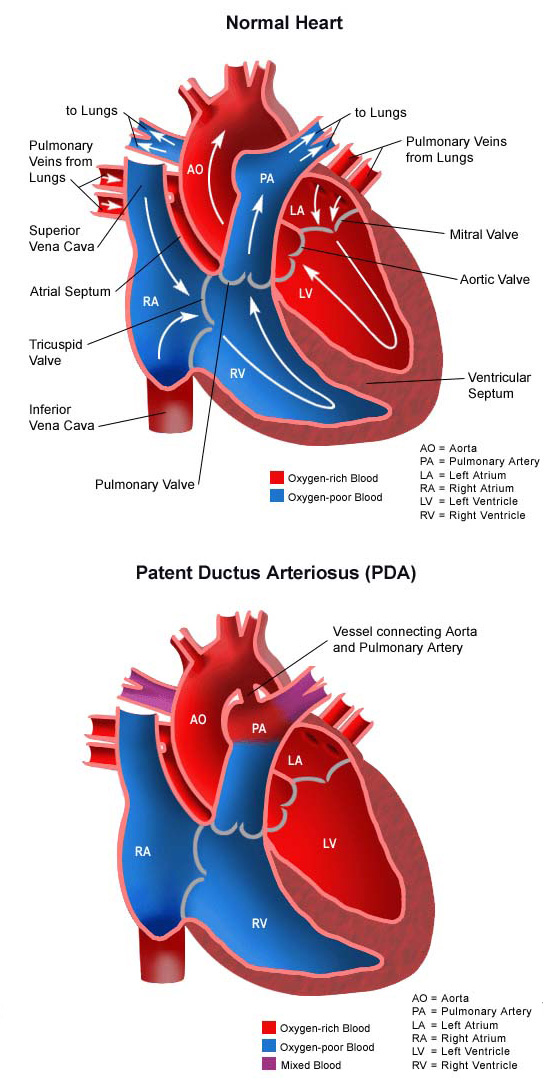

PDA Pathophysiology and Anatomy

What is this PDA and why do the doctors want to close it

PATENT DUCTUS ARTERIOSUS PDA IN CHILDREN Dr Gaurav Agrawal

What is PDA in Newborn Babies

Patent Ductus Arteriosus PDA in the newborn

Patent Ductus Arteriosus PDA Conditions amp Treatments Minnesota

Patent Ductus Arteriosus Pediatric Heart Specialists

Patent Ductus Arteriosus PDA for Parents Nemours Kidshealth

Patent Ductus Arteriosus PDA Symptoms and Risk Factors Dr Raghu

Pediatric Patent Ductus Arteriosus PDA

Patent Ductus Arteriosus Children s Hospital of Orange County